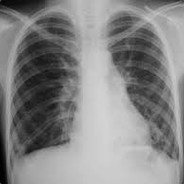

нимок Легких При Бронхите Фото

Снимок Легких При Бронхите Фото 140 фотографий